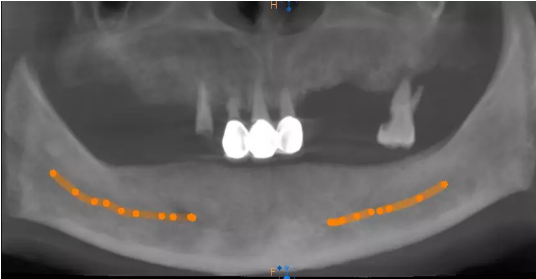

患者术前口腔全景片

周炜院长为韦爷爷作了全套系统检查,又给爷爷拍摄口腔全景片,从片子里可以清晰的看到贾叔叔的口腔里几乎已经无一颗好牙。